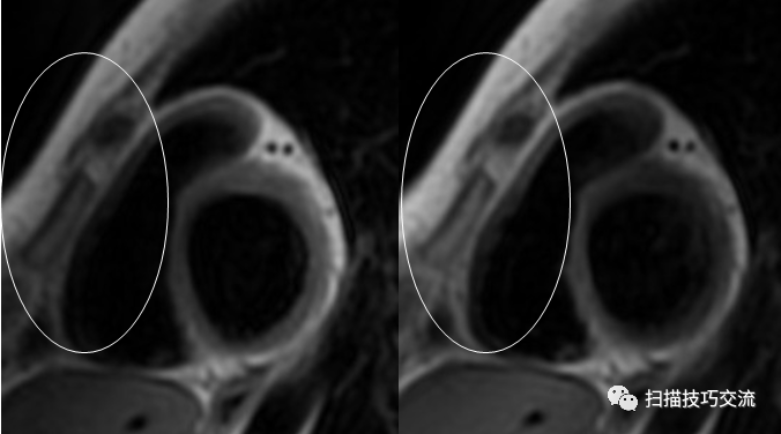

左图,双翻转黑血,匀场未勾选Localized TG;右图,双翻转黑血,匀场勾选Localized TG。勾选之后改善了白圈处的阴影。